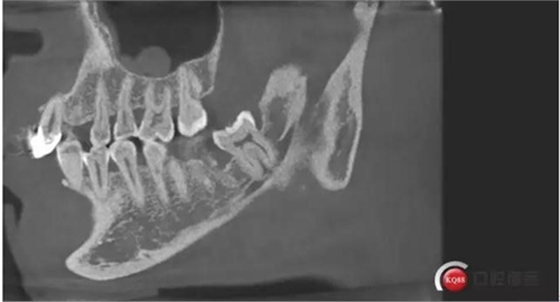

下面CBCT,可以看到兩個牙根的根尖三分之一在神經(jīng)管里面。

下面?zhèn)惹忻?p style="text-align: center;">